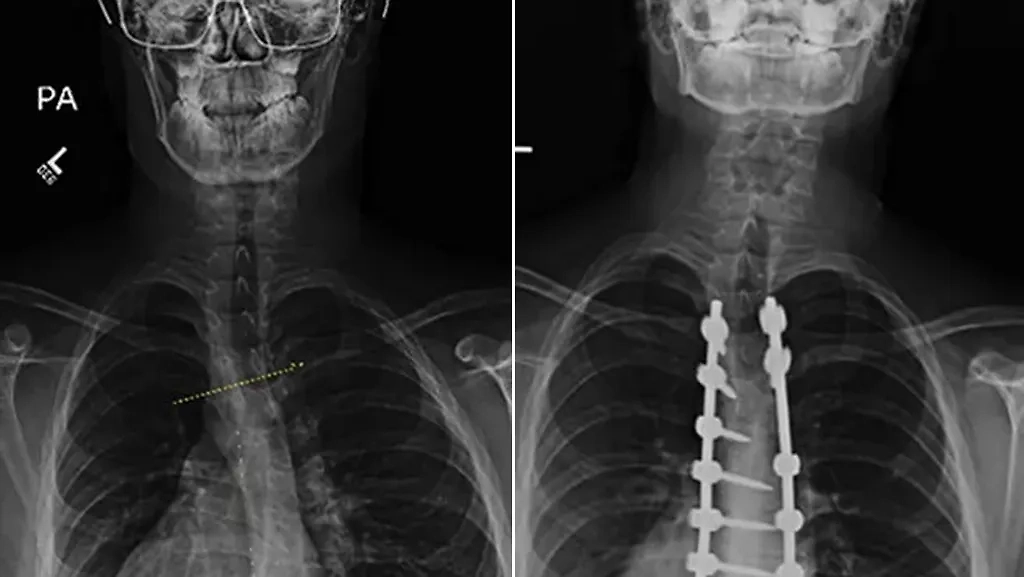

"Лечение ревматоидного артрита. До и после", — joshuas3.